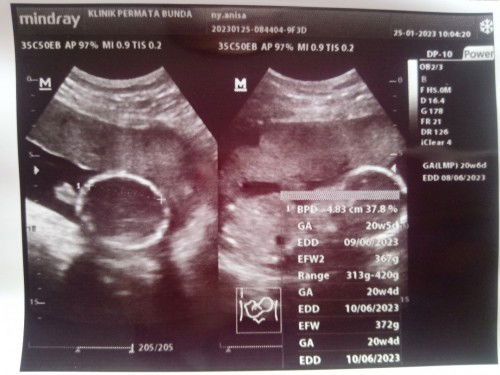

Usg pertama di usia 20week

Alhamdulillah dd utun sehat , semua nya normal bbj udah 370g